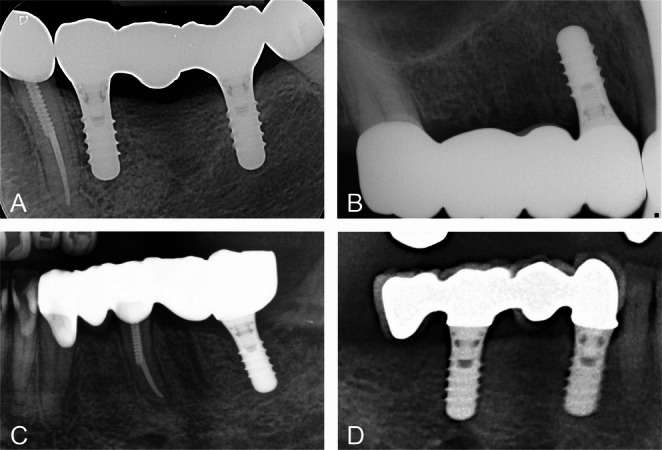

Materials and methods: 434 FDPs placed in 326 patients were selected from a prospective clinical long-term study. 213 FDPs were solely implant-supported, 154 FDPs tooth-implant supported, and 67 FDPs were cantilever FDPs. The most FDPs had 3-units (n = 315), 95 FDPs had 4-units, and 24 FDPs had more than 4 units. The most FDPs had a unit/abutment relation of ≤ 1.5 (n = 336), and 98 FDPs had a relation of > 1.5. Kaplan-Meier curves were used to estimate the survival probability of the FDPs for the variables type of FDP support, number of units and loading factor. Univariate log-rank tests were used to test for differences between groups within variables.

Results: The mean observation period was 4.27 years. In the observation period of up to 12.6 years 17 FDPs failed mainly through technical complications. The underlying causes were implant loss (n = 6), abutment tooth loss (n = 5), loosening of the abutment screw (n = 1), and extensive chipping (n = 5). Survival probability of all FDPs was ≥ 89,6% after 10 years. Log-rank tests revealed no significant differences between groups for all variables (support, number of units, and loading factor (p ≥ .339).

Conclusions: Because of their promising prognosis 4-unit FDPs placed on implants or a combination of tooth and implant can be recommended as an alternative to 3-unit FDPs. A higher number of implants in relation to FDP units does not improve the prognosis of FDPs.

Clinical relevance: Support, number of units and the loading factor do not influence the survival of FDPs. Therefore, 4-unit FDPs placed on implants or a combination of tooth and implant are a valuable treatment alternative to 3-unit FDPs.